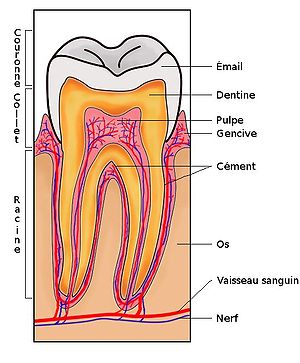

Son corps est essentiellement composé de dentine. Ce tissu est minéralisé à 70 % par l'hydroxyapatite. Les 30 % restant (dont 12 % d'eau) forment la trame organique, composée principalement de collagène. La dentine est perforée de micro-tubes ou tubulis dentinaires. Ceux-ci contiennent les prolongements des cellules dentaires, les odontoblastes. Ces cellules tapissent la périphérie de la cavité pulpaire. Elles synthétisent la dentine tout au long de la vie, de manière centripète, ainsi qu'à un rythme particulièrement lent.

Le tissu pulpaire assure leur innervation et leur vascularisation en provenance des racines dentaires. Les odontoblastes synthétisent en réponse à l'agression carieuse une dentine réactionnelle.

La couronne est recouverte d'émail, tissu minéralisé à plus de 97 %. Il est moins épais sur les dents temporaires. La racine est recouverte de cément, où s'enracinent les fibres collagèniques et élastiques du ligament alvéolo-dentaire ou desmodonte.

Ce ligament forme avec l'os une véritable articulation et renferme des cellules de régénération osseuse, ligamentaire et cémentaire. Il est richement innervé par des récepteurs mécaniques, propriocepteurs, qui renseignent le dispositif nerveux central sur la position exacte des dents et la pression exercée par les muscles masticateurs.

La dent est implantée dans l'os alvéolaire par une à trois racines (quelquefois plus). Les racines dentaires se terminent par un apex dont l'ouverture de moins de 1 mm permet la vascularisation et l'innervation de la dent (par le nerf mandibulaire).